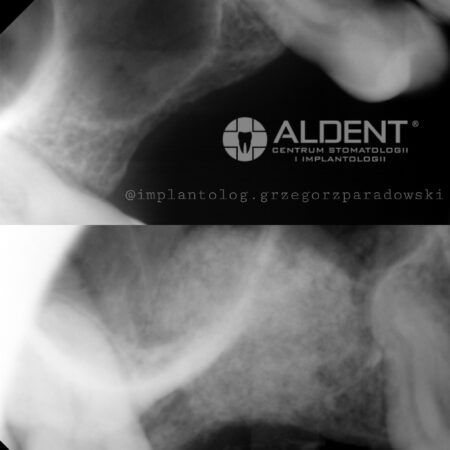

Podnoszenie zatok szczękowych to procedura, która pozwala na zwiększenie objętości tkanki kostnej w zatokach szczękowych, co jest kluczowe dla możliwości przeprowadzenia zabiegów implantologicznych w miejscach o niedostatecznej ilości kości.

- Przed zabiegiem przeprowadzamy szczegółową konsultację i diagnostykę, aby dokładnie ocenić anatomię zatok szczękowych i zaplanować odpowiednią metodę podnoszenia zatok.

- Metoda Otwartego Podnoszenia Zatok

- Metoda ta jest stosowana, gdy konieczne jest znaczące zwiększenie objętości tkanki kostnej. Chirurg wykonuje niewielkie nacięcie w dziąśle, aby uzyskać dostęp do zatoki szczękowej. Następnie delikatnie unosi błonę zatoki i wprowadza materiał kościozastępczy, który stymuluje tworzenie nowej tkanki kostnej.

- Metoda Zamkniętego Podnoszenia Zatok

- Metoda ta jest mniej inwazyjna i jest stosowana, gdy wymagana jest niewielka ilość dodatkowej tkanki kostnej. Materiał kościozastępczy wprowadzany jest przez otwór po ekstrakcji zęba lub przez specjalnie przygotowany otwór w kości.